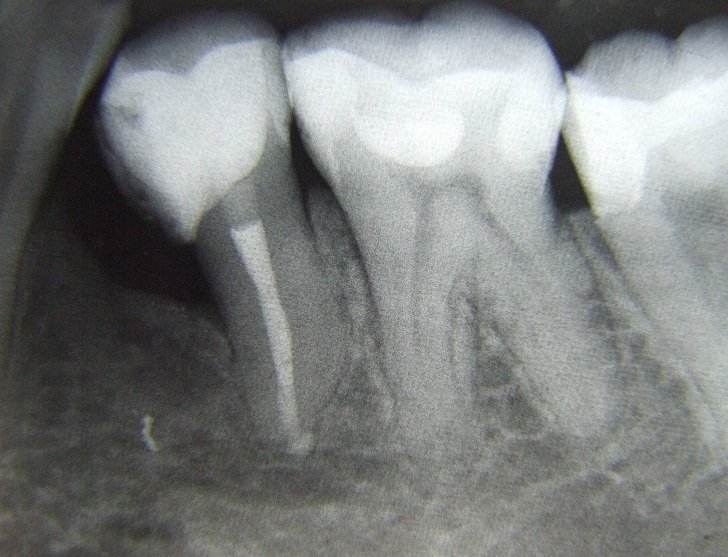

Desi nu este de dorit, uneori se constata prezenta unor leziuni extinse (granuloame, chisturi) care daca nu sunt rezolvate corespunzator, pun in pericol viabilitatatea dintelui.

Din nou tratamentul sub microscop optic efectuat de catre specialistii endodonti poate duce la salvarea dintelui.